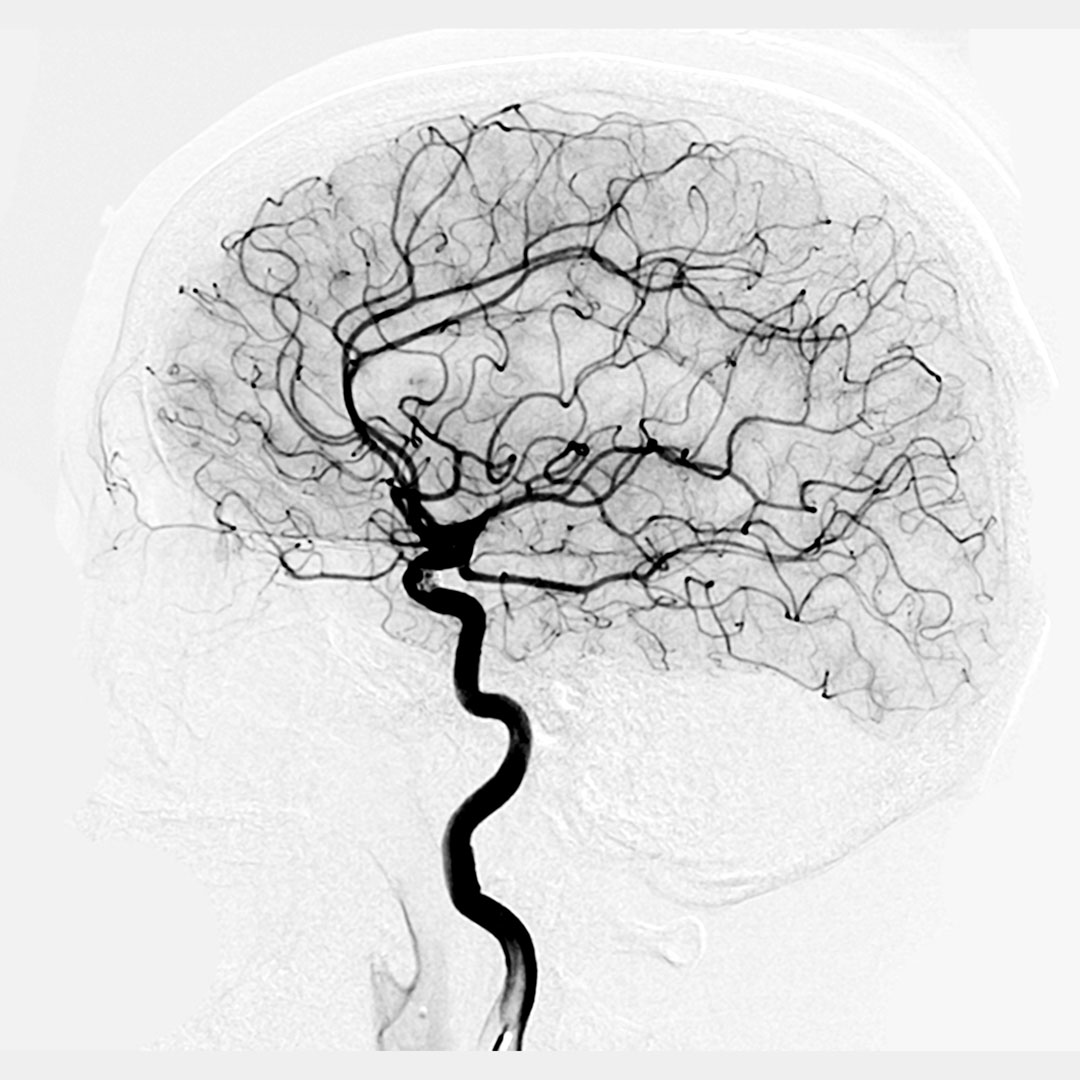

Cerebral Angiography

Cerebral angiography was pioneered by the Portuguese neurologist Egas Moniz in 1927 and has since continued to evolve to be the essential imaging for cerebrovascular pathology, frequently yielding more telling diagnostic images than conventional MRI or CT scans. With the expansion of endovascular techniques cerebral angiography has further allowed for immediate intervention with embolization, coiling and even clot retrieval.

It also produces some incredible images of the cerebral circulation!